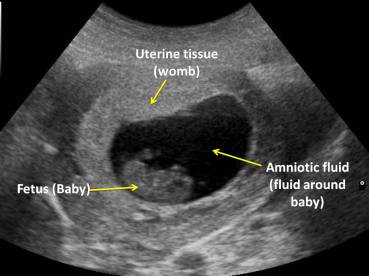

This image shows the baby’s position and movements. Hard tissues such as bone show up as white areas on the image, and soft tissues appear grey and speckled. Fluids (such as the amniotic fluid that the baby lies in) do not reflect any echoes, so appear black. It is the contrast between these different shades of white, grey and black that allows your doctor to interpret the images.